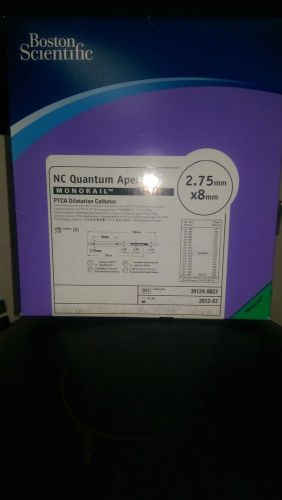

Boston Scientific NC Quantem Apex #39124-0827